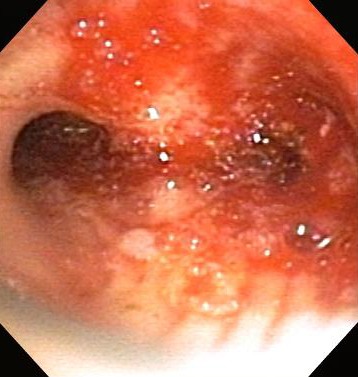

Contact or non-contact technique in which a high-frequency alternating electric current is delivered to the airway tissue for the relief of malignant and non-malignant CAO. [Figure caption and citation for the preceding image starts]: Post-lung transplant anastomotic bronchial stenosisFrom the collections of Jose Fernando Santacruz MD, FCCP, DAABIP and Erik Folch MD, MSc; used with permission [Citation ends].

[Figure caption and citation for the preceding image starts]: Post-lung transplant anastomotic bronchial stenosis: electrocautery radial incisionFrom the collections of Jose Fernando Santacruz MD, FCCP, DAABIP and Erik Folch MD, MSc; used with permission [Citation ends].

The effect on the airway tissue depends on the power used, the application time, the contact surface area, and the tissue type. The heat generated by the electric current is proportionally related to tissue resistance, and inversely related to tissue vascularity and moisture content.

Can be used in emergency situations and is an excellent tool for rapid endobronchial debulking, with a reported rate of lumen restoration of approximately 90%, and symptom relief of 70% to 97%.